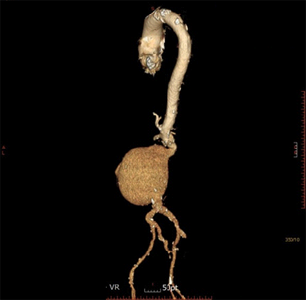

복부 대동맥류

술전 CT 및 복부대동맥 내 스텐트 삽입술 후 CT

술전 CT

복부대동맥 내 스텐트 삽입술 후 CT